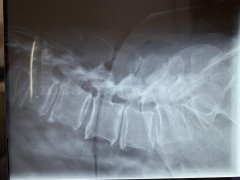

Fractura toracolumbar

Fractura de columna cervical